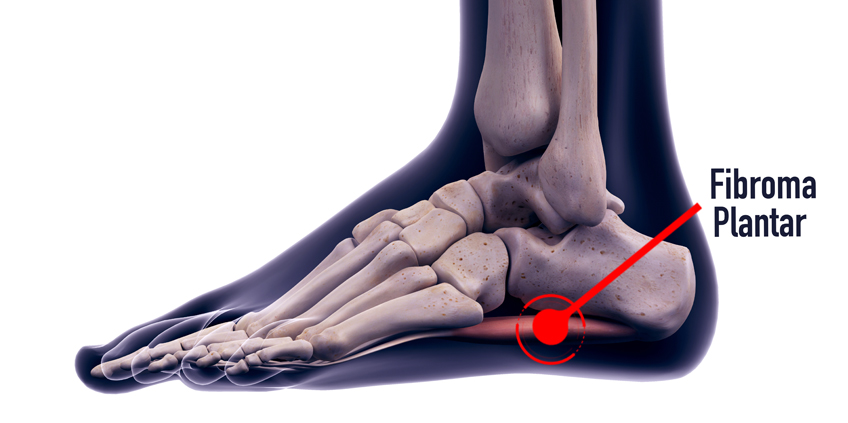

Si has encontrado un bulto en el arco plantar, es muy probable que haya desarrollado un fibroma plantar (también conocido como fibromatosis plantar cuando se desarrollan en conjunto). Esta patología se encuentra enmarcada dentro de la enfermedad de Ledderhose y es un crecimiento anormal de la fascia plantar acompañado con un crecimiento benigno o nodular, afectando con mayor frecuencia a varones.

Actualmente se desconoce su origen, pero los últimos estudios afirman que tienen íntima relación con microtraumatismos de repetición. Esto se debe a que cuando caminamos o practicamos cualquier actividad deportiva, un exceso de arco plantar (pie cavo) o un desplome hacia el interior del arco plantar (pie valgo) provocan una mayor tensión en la fascia plantar, ya que ambos comparten una disminución del apoyo lateral externo. Este estiramiento excesivo puede conducir a la formación de los fibromas condicionado por una fuerte predisposición genética.